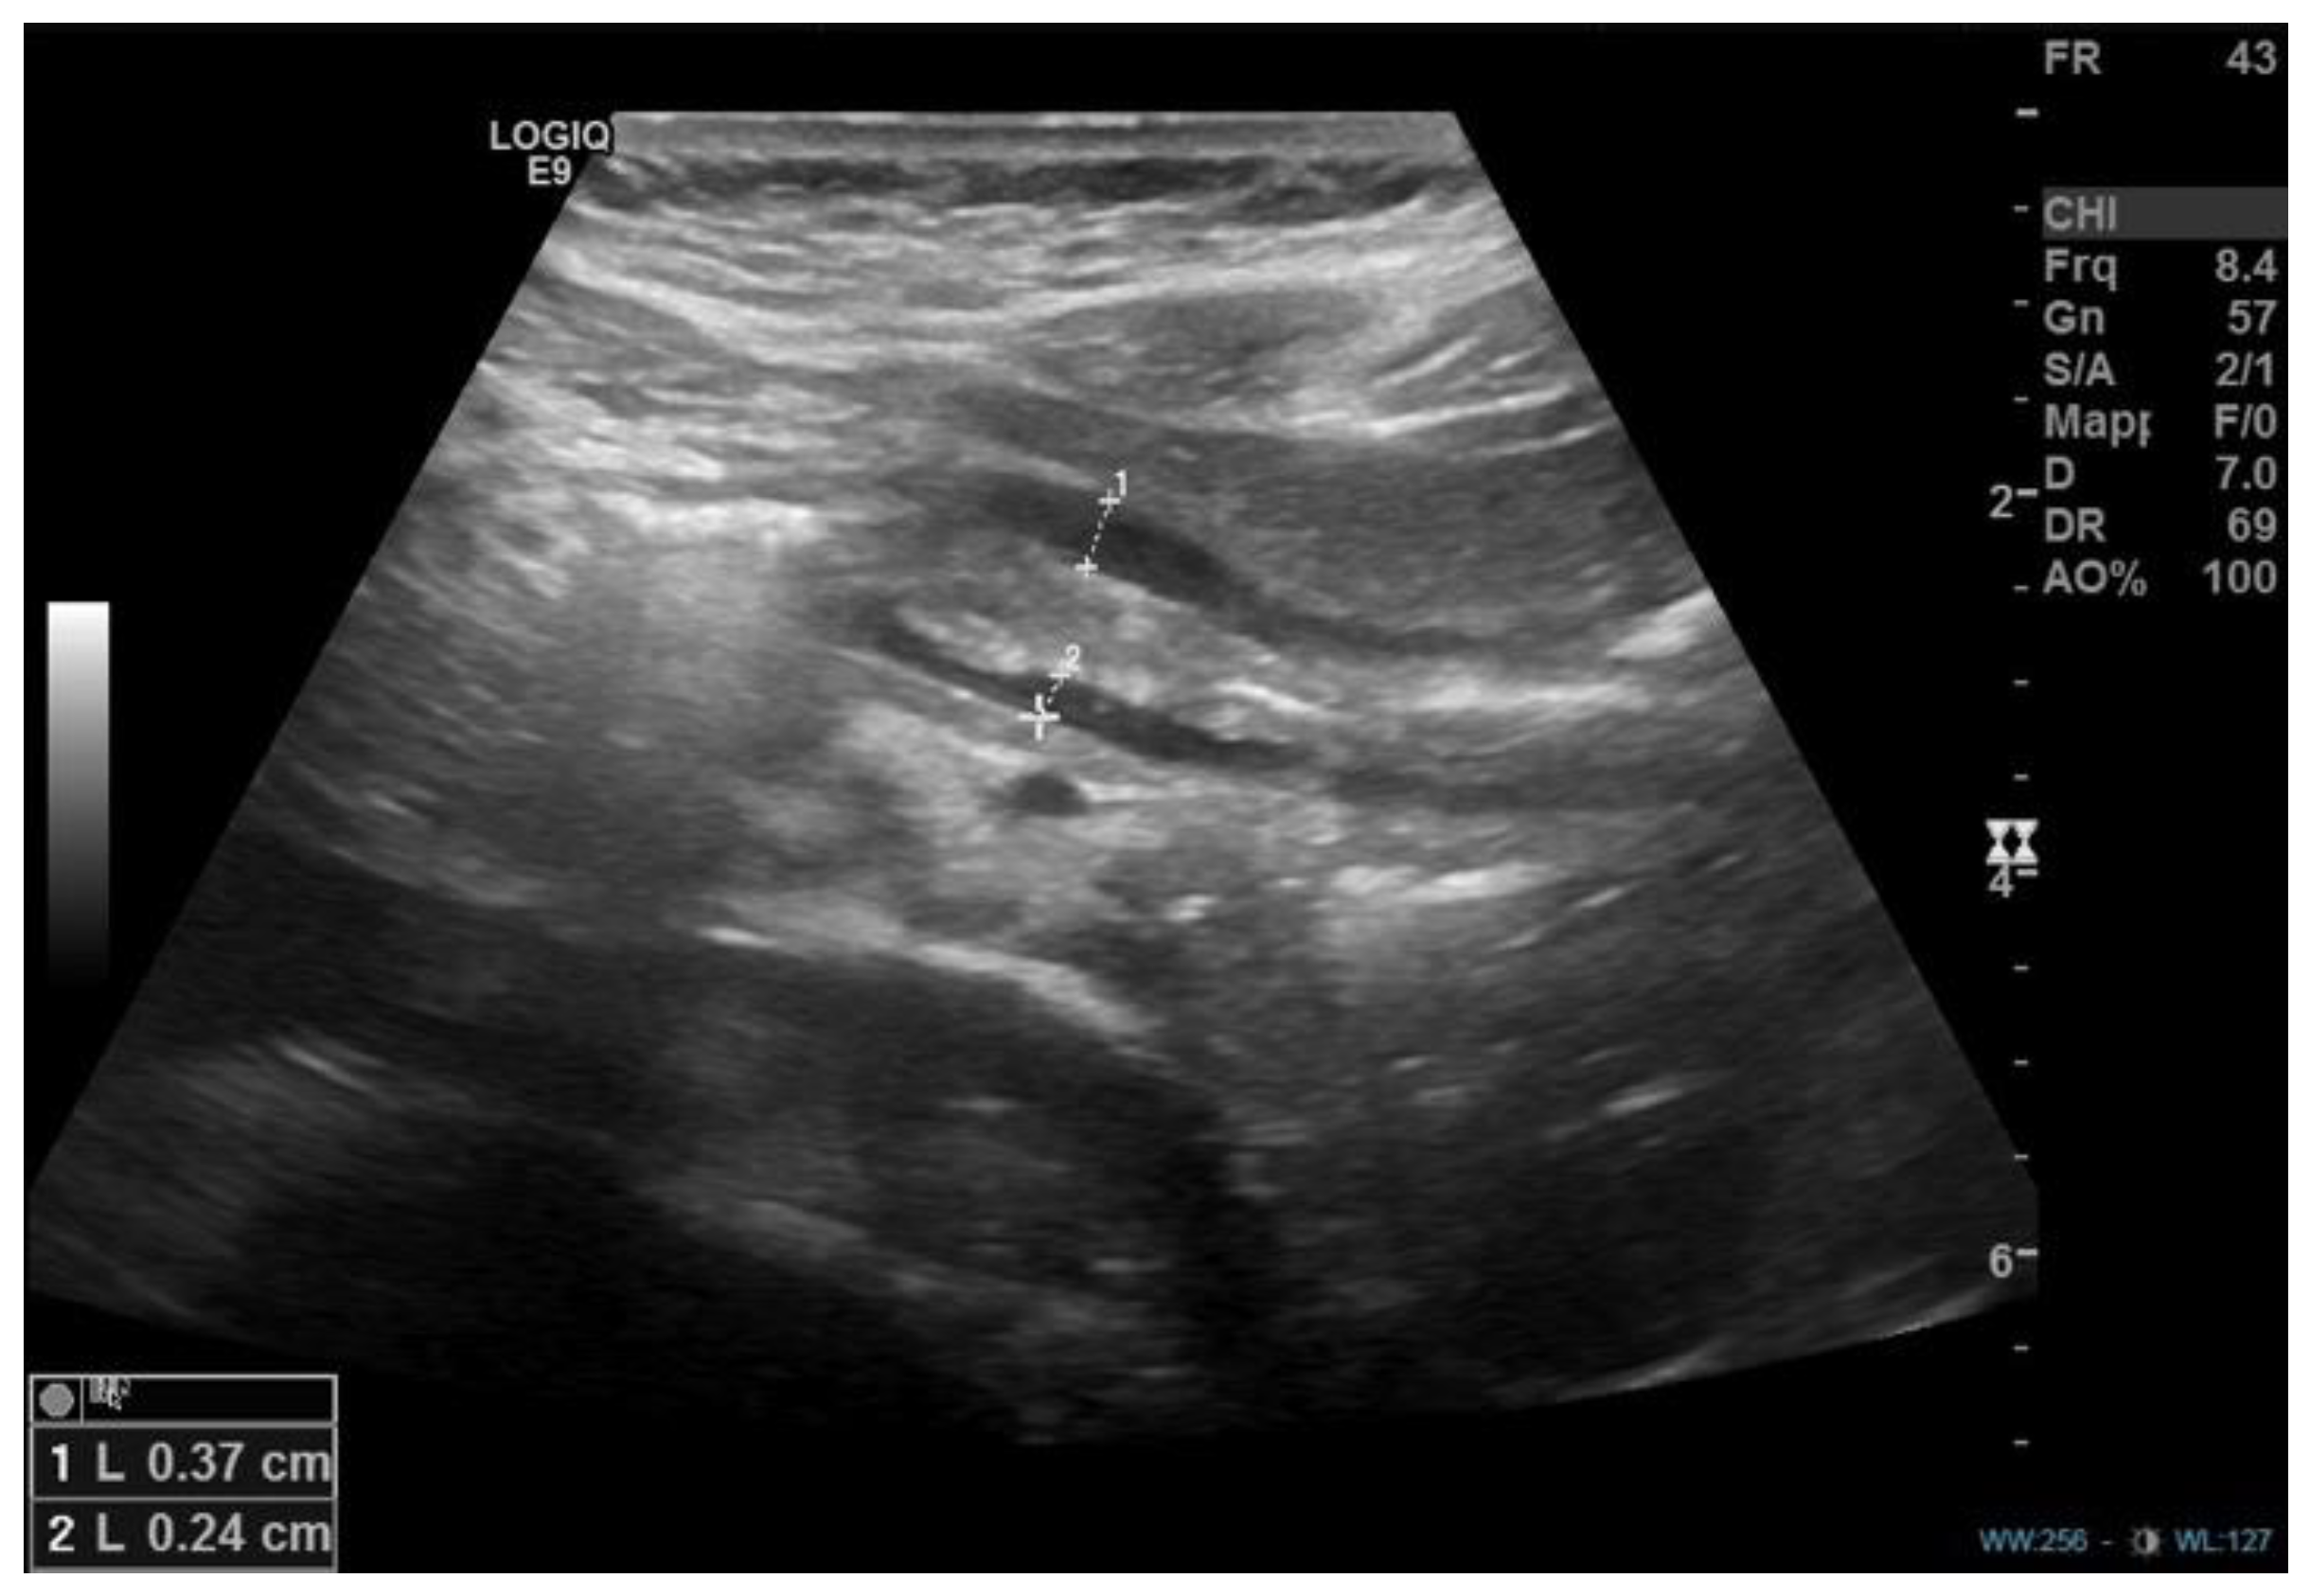

- Blumhageen, J.; Krauter, D.; Rosenbaum, D.; Weinberger, E. Sonographic diagnosis of hypertrophic pyloric stenosis. Am. J. Roentgenol. 1988, 150, 1367–1370. [Google Scholar] [CrossRef] [PubMed]

- Dias, C.; Swinson, S.; Torrão, S.; Gonçalves, L.; Kurochka, S.; Vaz, C.P.; Mendes, V. Hypertrophic pyloric stenosis: Tips and tricks for ultrasound diagnosis. Insights Imaging 2012, 3, 247–250. [Google Scholar] [CrossRef]

| Mahalik et al. [15], 2010 | 1 | 4,5 years | Non bilious vomiting | US, UGI series, CT scan | - | OP |

| Boybeyi et al. [16], 2010 | 11 | 3,6 (2–8) years (mean age, range) | Vomiting (5 cases) Vomiting + abdominal pain (4 cases) Vomiting + weight loss (2 cases) | US + UGI series (6 cases), UGI series (5 cases), EGDS | Gastric edema and hyperemia (2 cases) | EBD (4 cases)–EBD + B-I (1 case)–B-I (6 cases) |

| Bajpai et al. [17], 2013 | 1 | 8 years | Non bilious vomiting and poor growth | US and X-Ray, EGDS, CT scan, UGI series | - | HMP + temporary jejunostomy |

| Al-Mayoofet al. [18], 2016 | 1 | 7 months | Vomiting, weight loss | UGI series, US | - | OP |

| Bartlett et al. [19], 2018 | 1 | 12 years | Vomiting, failure to thrive | EGDS, US. | Previous history of eosinophilic esophagitis. Gastritis. | EBD + Botulinum injection (failure) HMP + temporary gastrostomy |

| Plessi et al. [14], 2021 | 1 | 12 years | Vomiting, growth failure (underlying diagnosis: Down’s Syndrome) | Abdominal US, UGI series (2), MRI, EGDS (2) | - | EBD + electrosurgical incisions (failure), distal gastrectomy with Roux-en-y reconstruction |

| Iacoviello et al. [21], 2022 | 1 | 3 years | Vomiting, rumination and weight loss | Abdominal US and X-Ray, UGI series (2), CT scan, EGDS, MRI. | - | EBD (failure) OP |